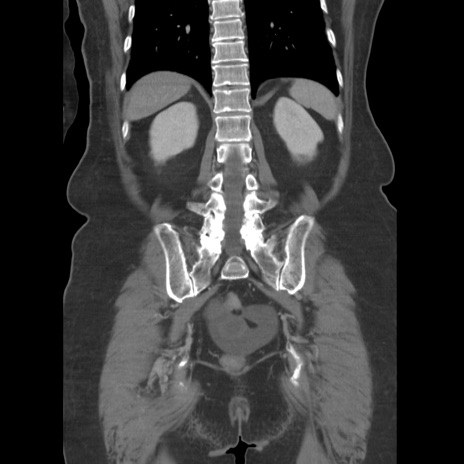

症例19(冠状断像)

【症例】80歳代女性

【主訴】下腹部痛

【現病歴】約8時間前より下腹部痛の出現あり、救急外来受診。

【既往歴】両側付属器切除

【身体所見】意識清明、下腹部正中に手術痕あり、その部位に一致して圧痛と反跳痛あり。腸蠕動音は亢進。

【データ】WBC 9300、CRP 0.15